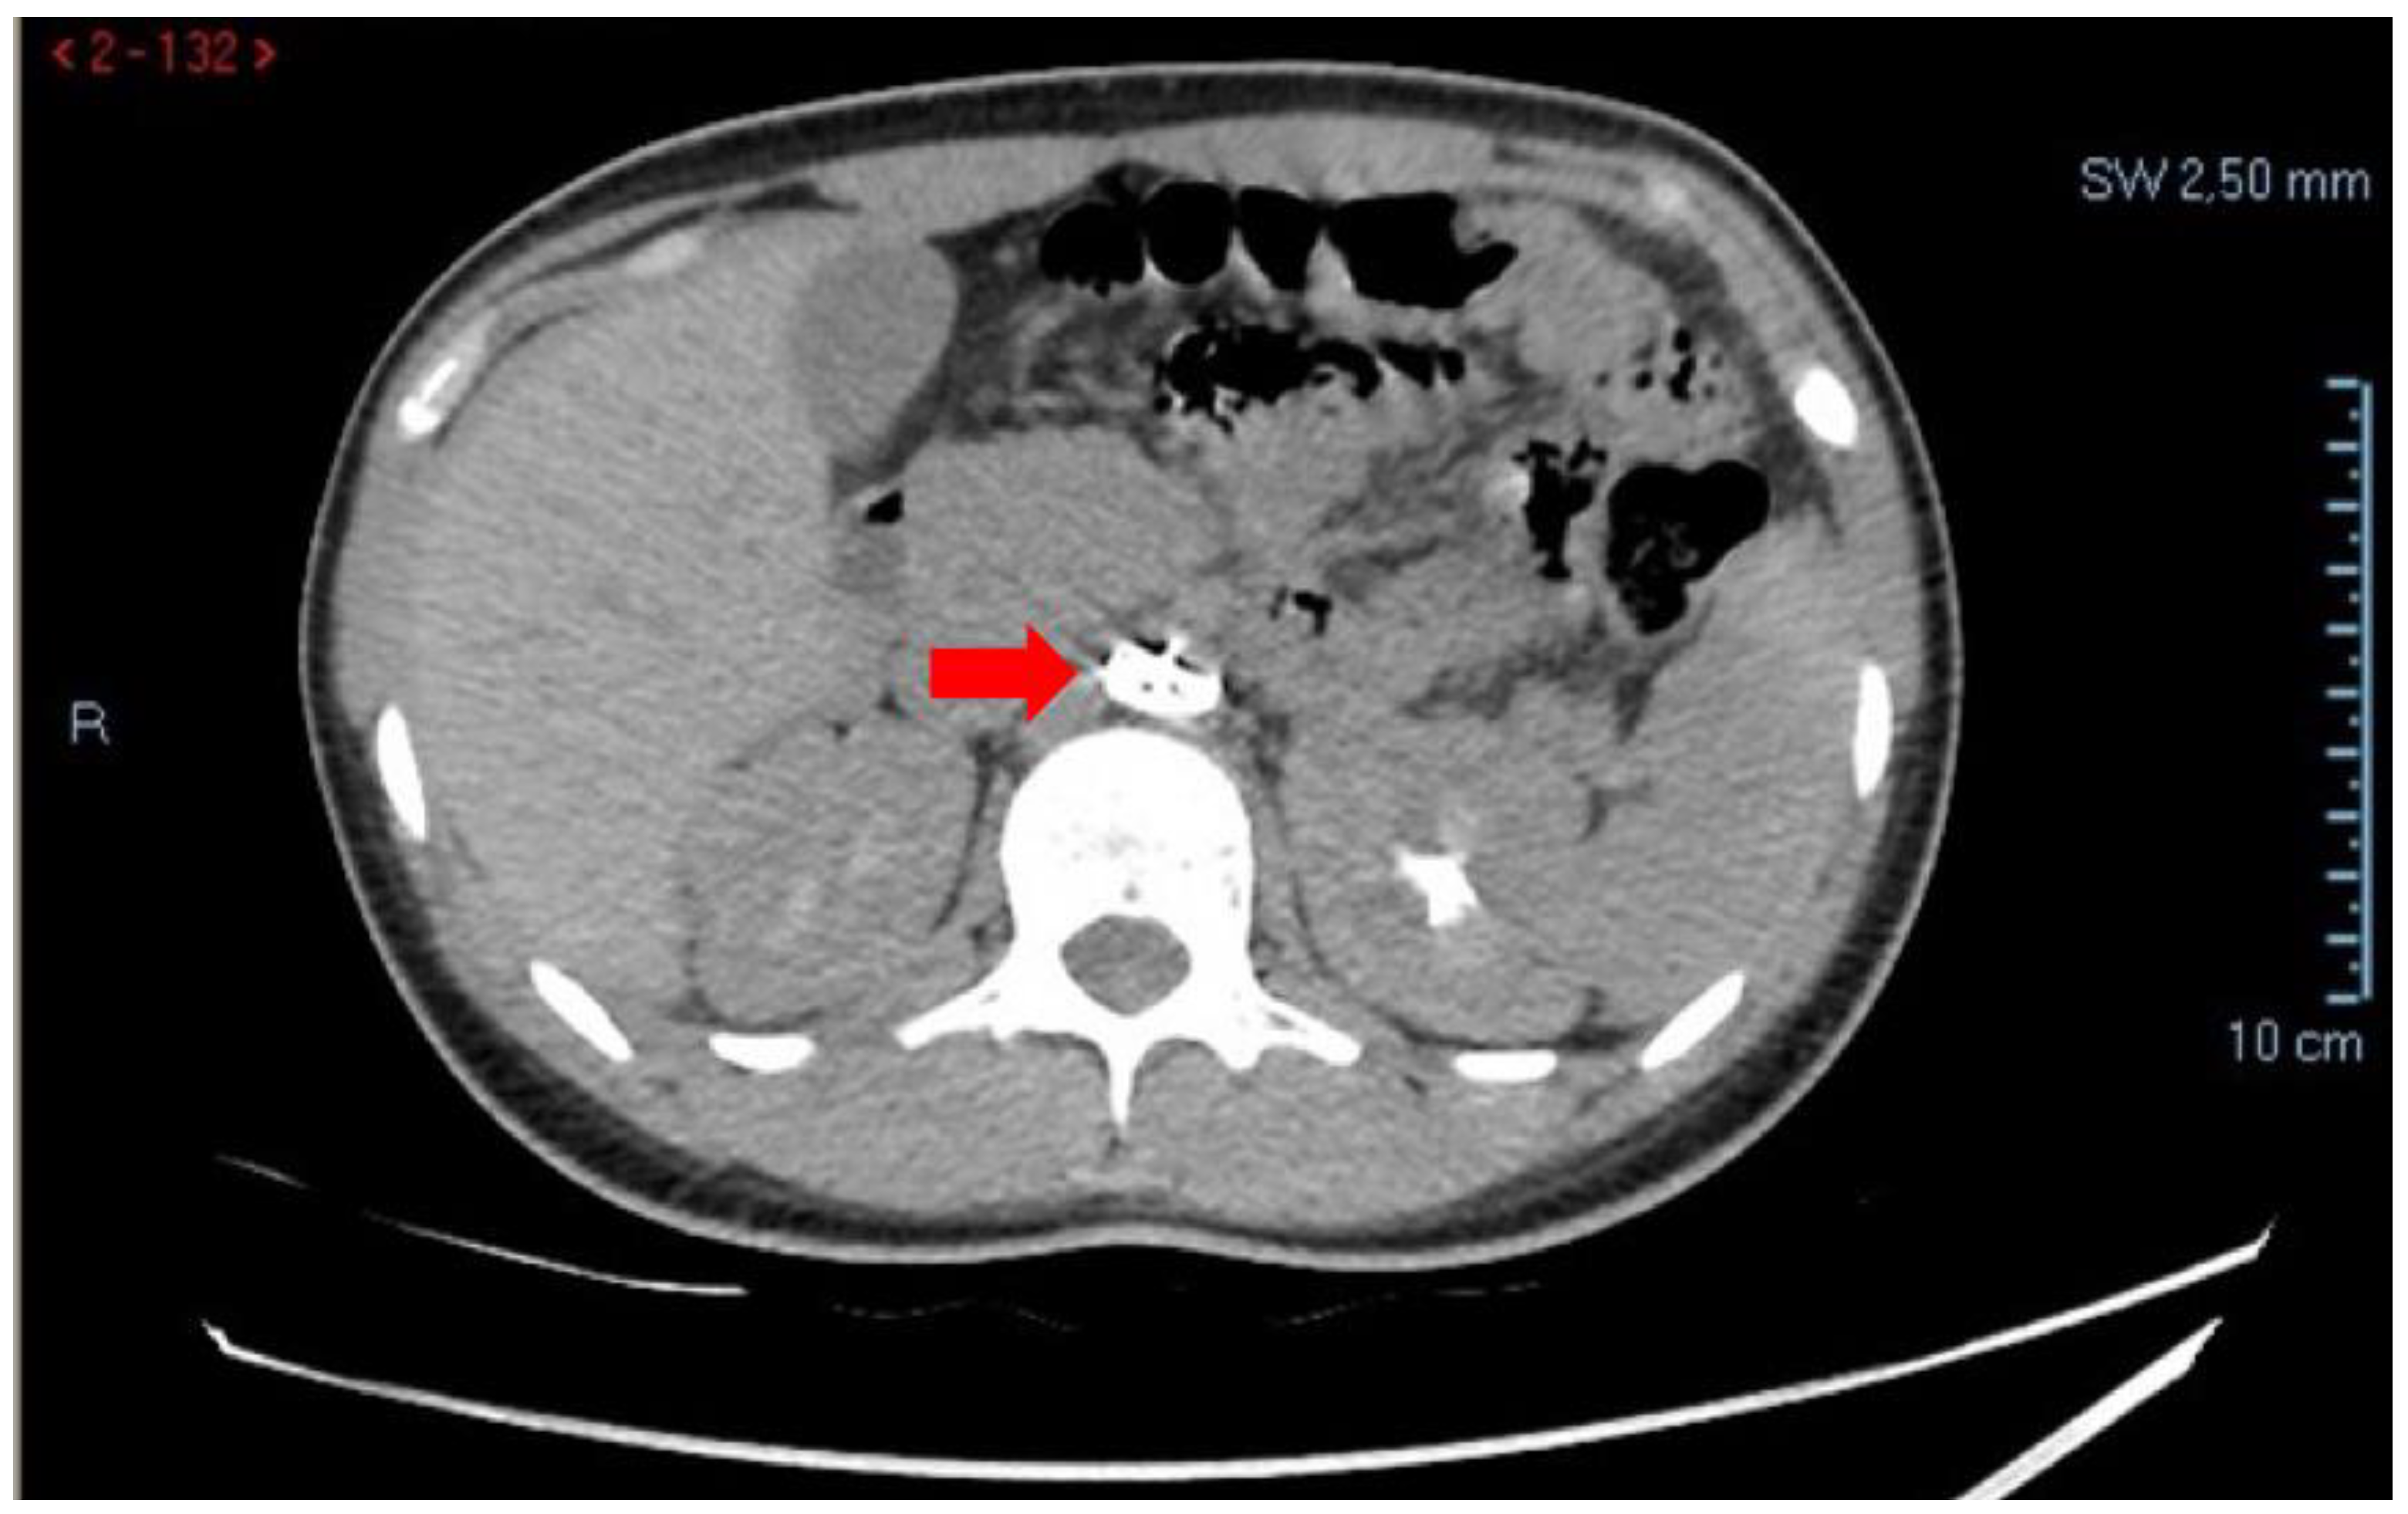

Given the persistence of abdominal pain, contrast-enhanced CT of the abdomen and thoracic aorta was performed. Imaging demonstrated hemoperitoneum secondary to a hemorrhagic ovarian cyst, with blood collection in the Douglas pouch and peritoneal recesses. Incidentally, CT also revealed migration of the Amplatzer device into the infra-renal abdominal aorta, with preserved patency of the renal arteries and no evidence of vascular obstruction or ischemia (Figure 1).

Figure 1. Contrast-enhanced CT of the abdomen demonstrating migration of the Amplatzer occluder into the infra-renal abdominal aorta (arrow), incidentally detected during evaluation for acute abdominal pain.